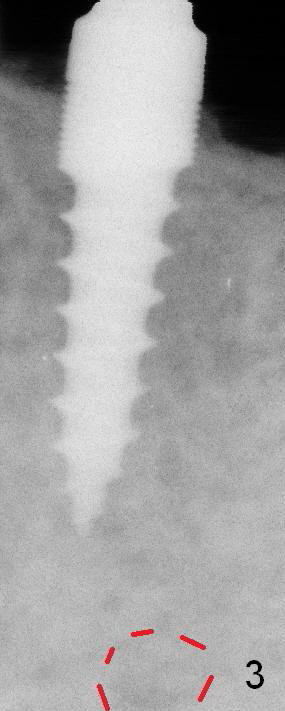

Immediately (Fig.3,4) and 3 months (Fig.8) post placement of 3x11 mm 1-piece implant at #20 (Fig.3) and 4.5x10 and 4.5x8 mm implants at #19 and 18, respectively.